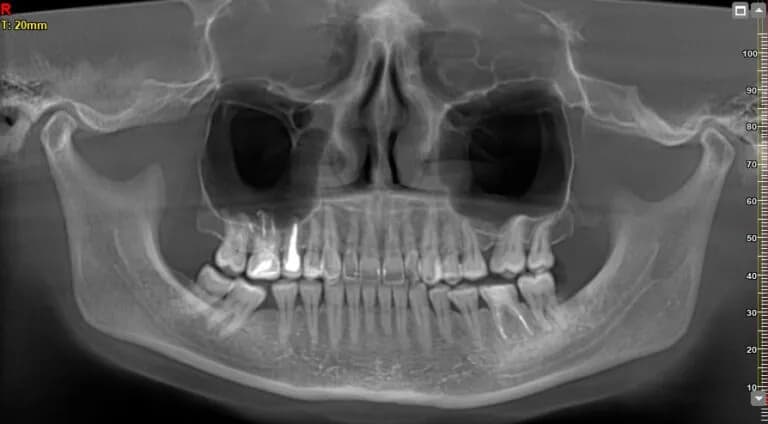

Bez względu na wiek, pantomogram na NFZ jest dostępny dla pacjentów, którzy spełniają określone kryteria. Dorośli mogą skorzystać z tego badania, jeśli są w trakcie leczenia endodontycznego lub protetycznego. W takim przypadku, wystarczy skierowanie od dentysty, aby uzyskać dostęp do tego świadczenia. To ważne, aby pacjenci byli świadomi, że pantomogram jest refundowany tylko w ramach określonych procedur medycznych.Dla dzieci i młodzieży w wieku od 5 do 18 lat, pantomogram w ramach NFZ jest dostępny bezpłatnie w uzasadnionych medycznie przypadkach. Obejmuje to sytuacje, takie jak podejrzenie nieprawidłowości rozwojowych zębów lub diagnostyka zmian chorobowych w kościach szczęki i żuchwy. W takich przypadkach, dzieci mogą korzystać z pantomogramu co trzy lata, co stanowi istotną pomoc w diagnostyce i leczeniu.

Dzieci mogą uzyskać bezpłatny pantomogram w ramach NFZ w określonych sytuacjach medycznych. Należą do nich przypadki podejrzenia nieprawidłowości rozwojowych zębów, zmiany chorobowe w kościach szczęki i żuchwy, zapalenie przyzębia oraz diagnostyka ognisk infekcji zębo- i niezębopochodnych. W takich przypadkach, pantomogram jest kluczowym narzędziem diagnostycznym, które może pomóc w wczesnym wykrywaniu problemów zdrowotnych. Ważne jest, aby rodzice byli świadomi tych okoliczności, aby mogli skorzystać z przysługujących im praw.- Podejrzenie nieprawidłowości rozwojowych zębów (np. zęby niewłaściwie rosnące)

- Zmiany chorobowe w kościach szczęki i żuchwy (np. torbiele lub guzy)

- Zapalenie przyzębia (stan zapalny tkanek otaczających zęby)

- Diagnostyka ognisk infekcji zębo- i niezębopochodnych (np. infekcje bakteryjne)